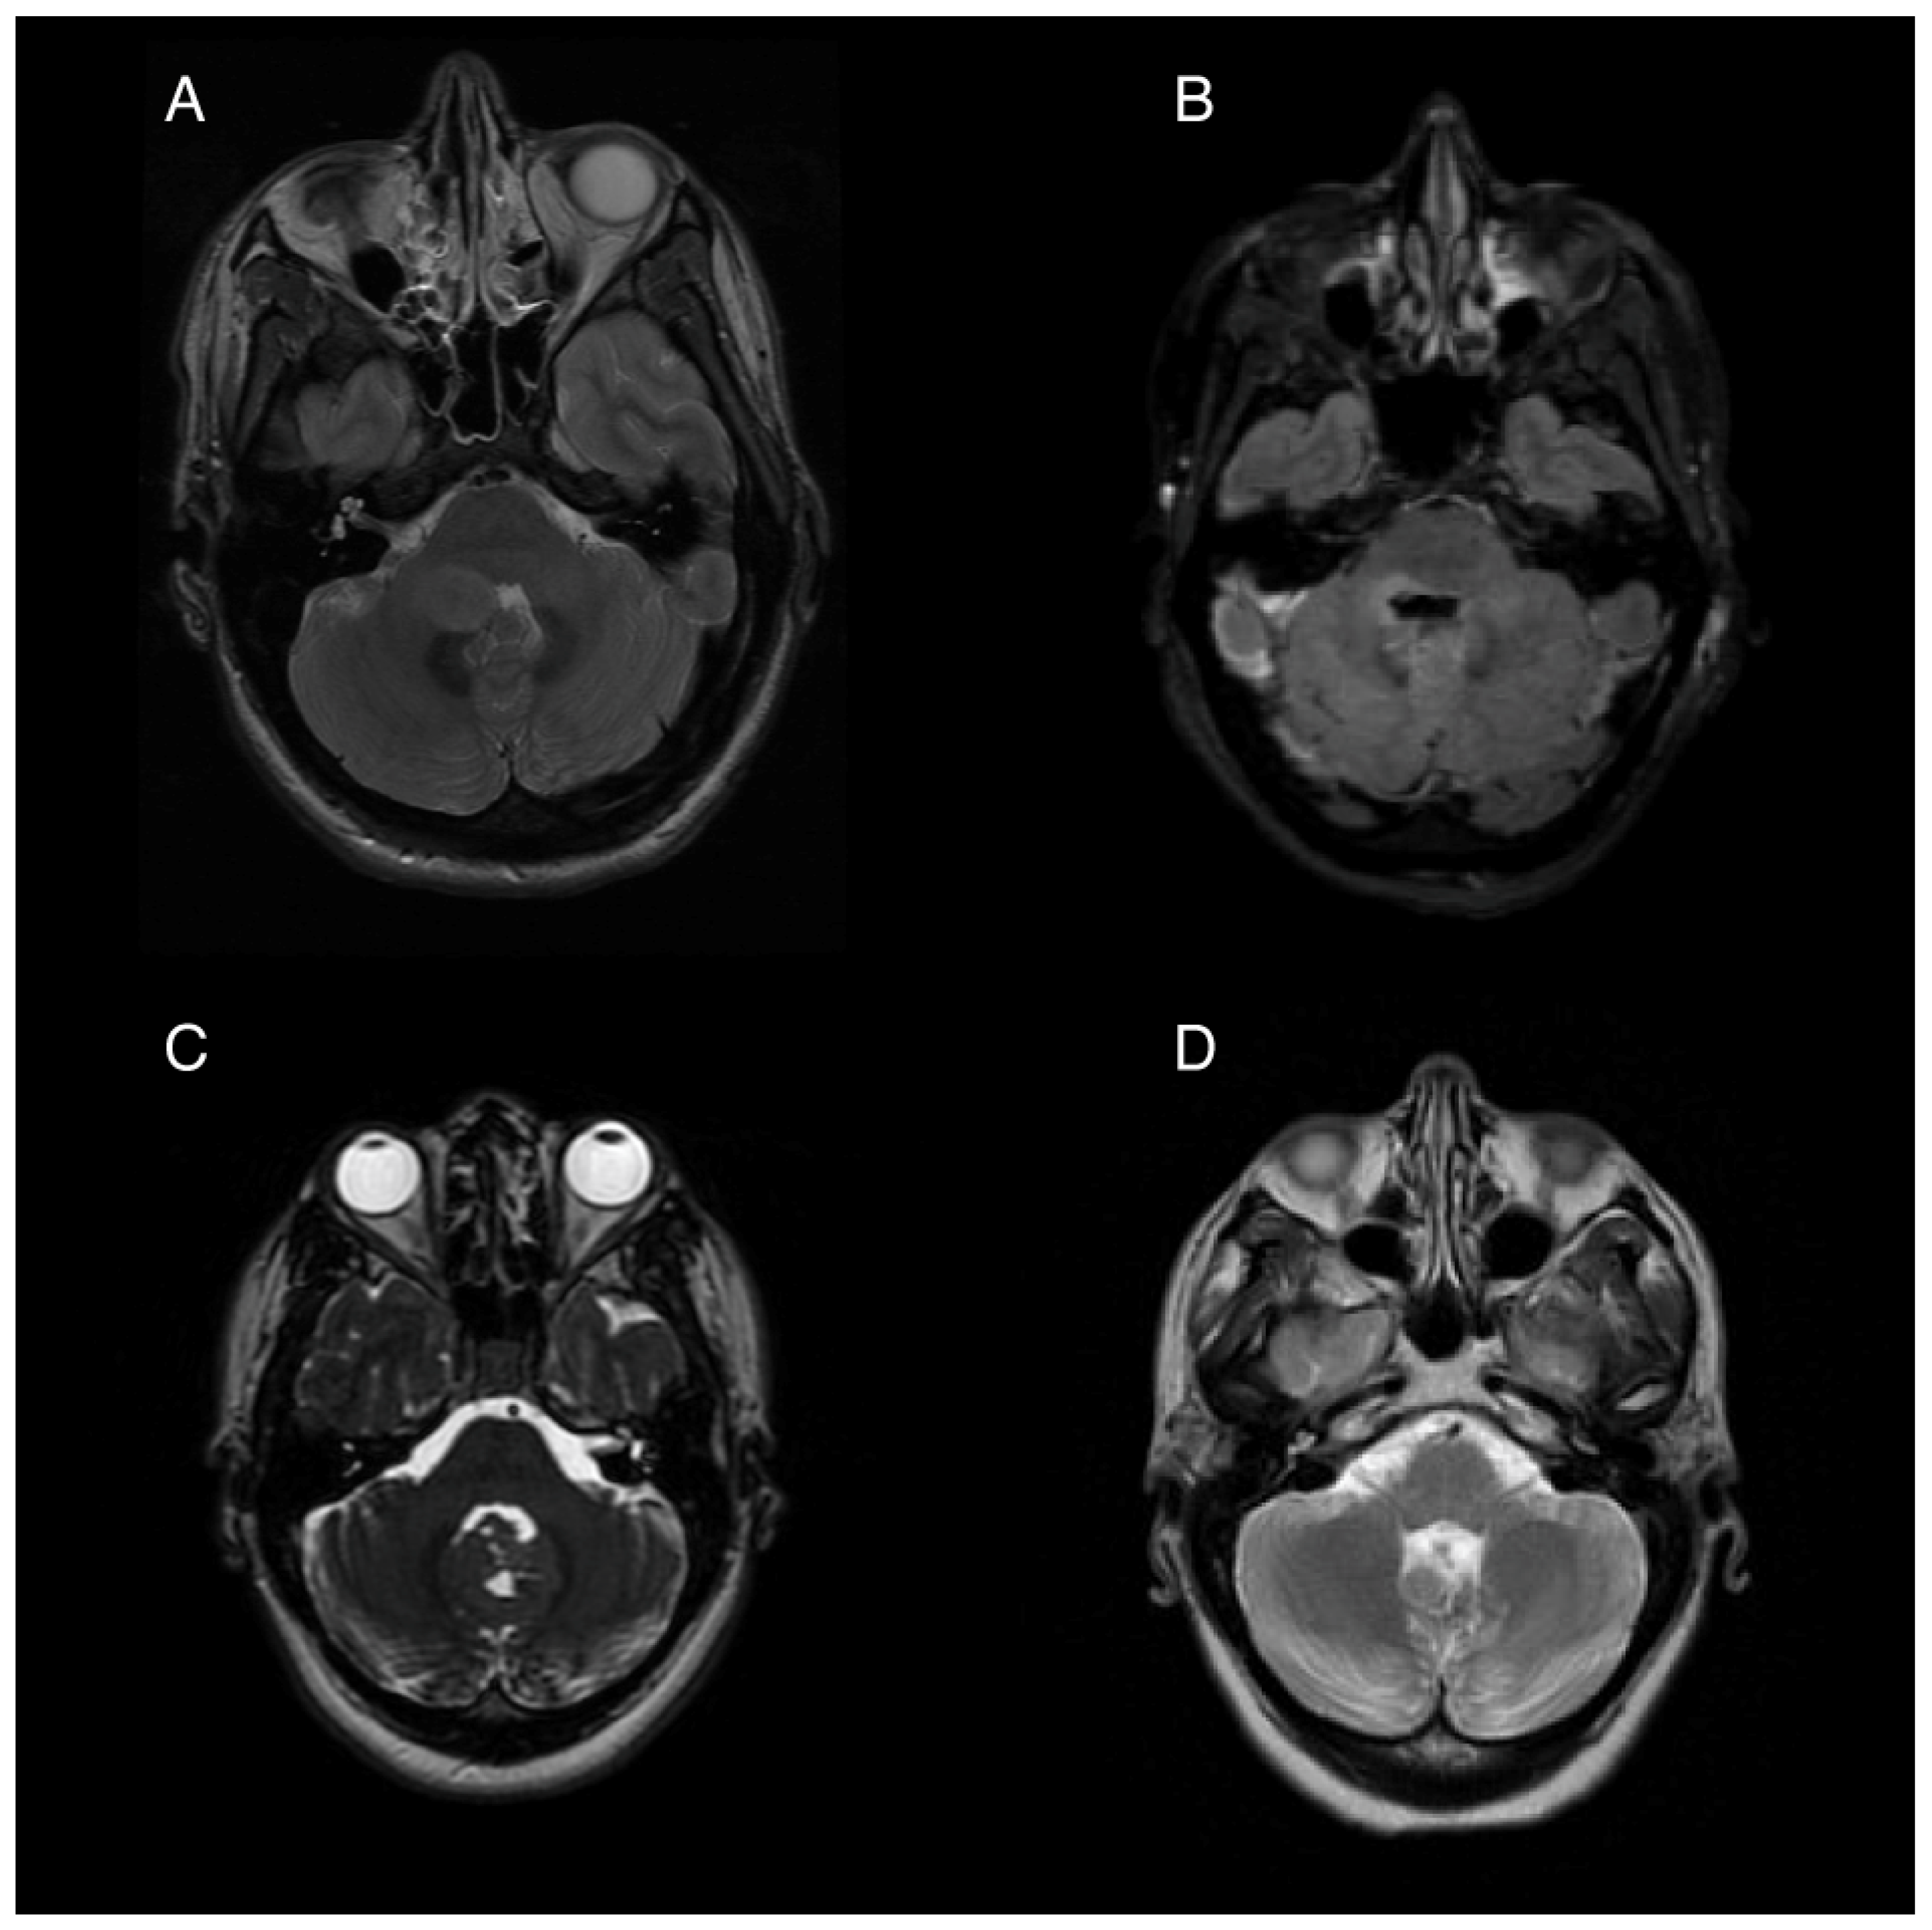

2.1. Patient 1

2.2. Patient 2